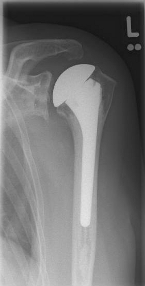

Conventional stem prostheses for omarthrosis and acetabular wear

right: anatomical shoulder prosthesis with glenoid replacement (Affinis type, Mathys company)